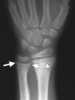

Fetal phenytoin toxicity